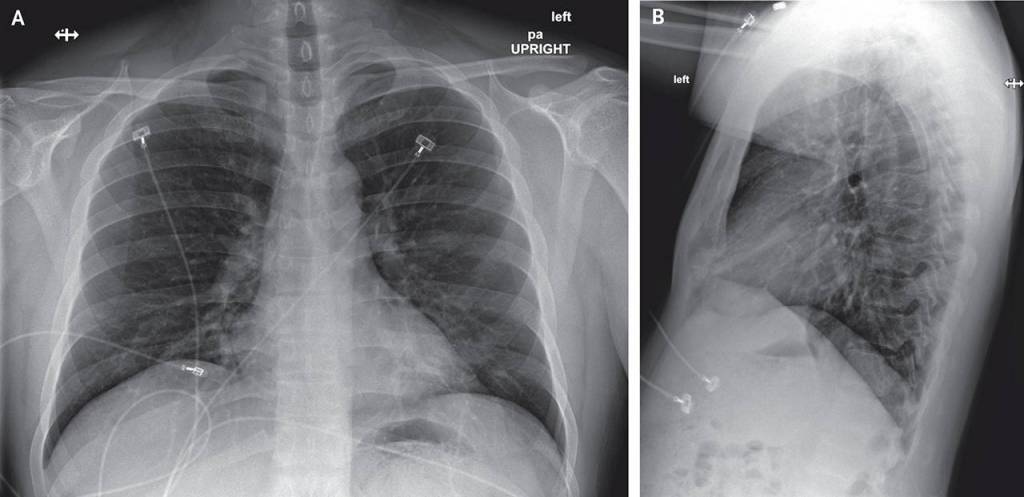

The article details the patient’s symptoms — everything from fatigue, nausea, diarrhea to a runny nose — over time and graphs his lab results. It shows X-rays of his lungs.